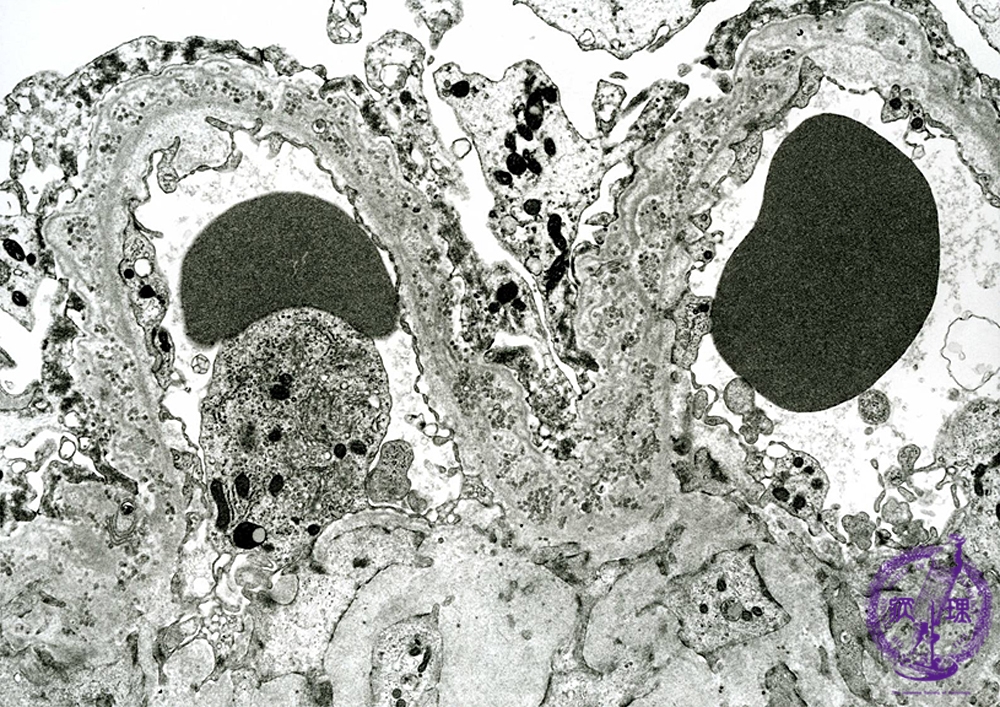

- ★(2)Membranous nephropathy

Electron microscopic findings: Stage IV. The presence of electron lucent deposits constitutes the main finding (red arrows).